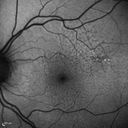

Reticular Macular Disease (Dry Macular Degeneration) - Infrared reflectance640 views85 year old woman with 20/25 vision OU and reticular macular disease00000

Reticular Macular Disease (Dry Macular Degeneration) - Infrared reflectance609 views85 year old woman with 20/25 vision OU and reticular macular disease00000